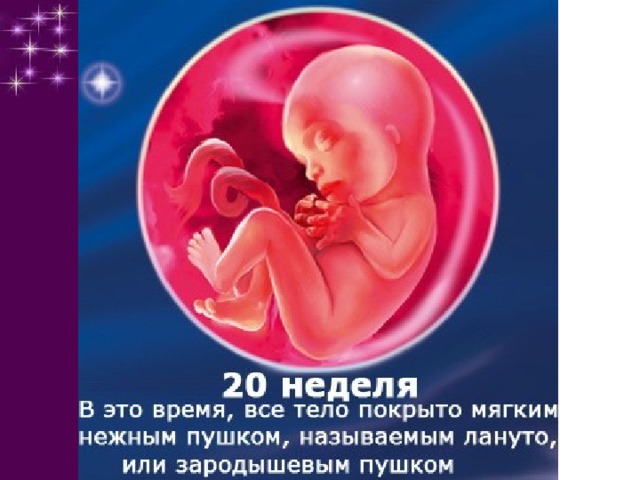

Важный этап: развитие малыша на 20-й неделе беременности

Раздел: Снимки-откровения